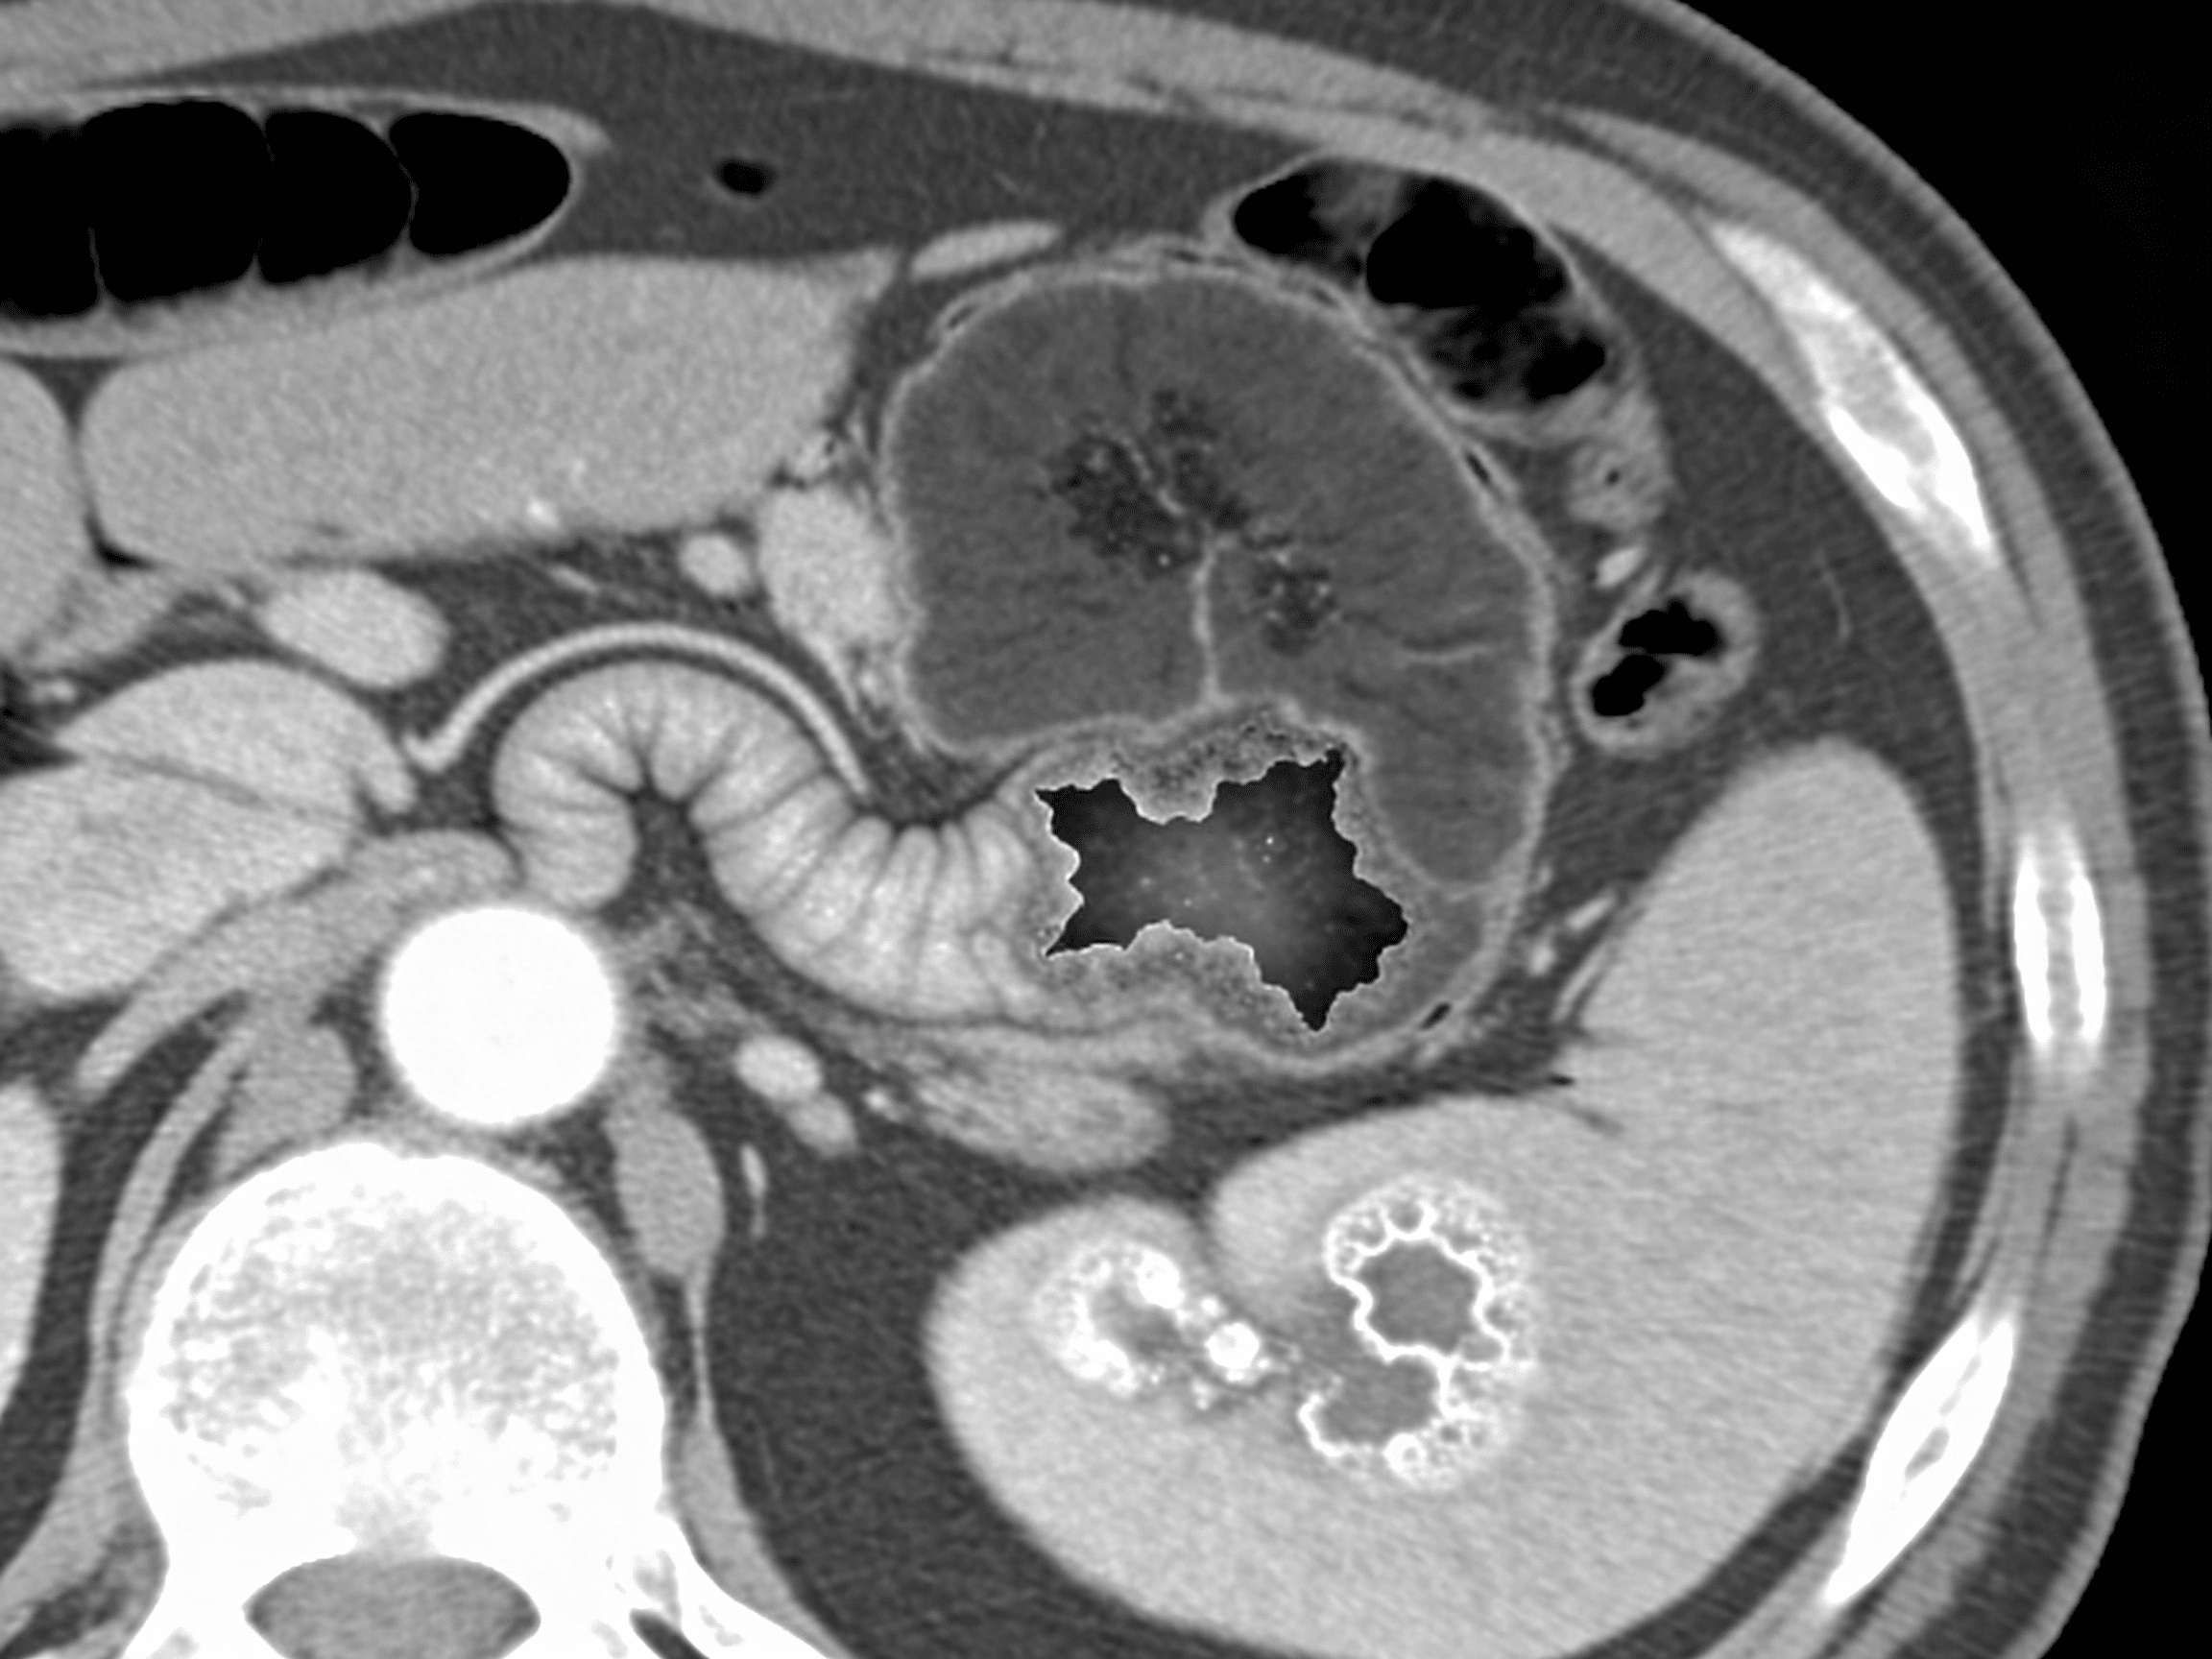

What does appendicitis look like on abdominal CT?

Appendicitis on CT shows appendiceal diameter >6mm, wall thickening >3mm, periappendiceal fat stranding indicating inflammation, and sometimes appendicolith (calcified fecal material) obstructing the lumen. Priority ER emergency physicians identify these findings with 95% sensitivity, immediately differentiating uncomplicated appendicitis requiring straightforward appendectomy from perforated appendicitis showing abscess, free air, or extraluminal fluid requiring different surgical approach with possible drain placement. Negative CT (normal appendix <6mm diameter, no inflammation) effectively excludes appendicitis, avoiding unnecessary surgery while prompting evaluation for alternative diagnoses.

Can abdominal CT detect internal bleeding from trauma?

Yes, contrast-enhanced abdominal CT detects internal bleeding with 98% sensitivity, identifying solid organ injuries (liver, spleen, kidney lacerations), active arterial bleeding appearing as contrast "blush" or extravasation, and bowel or mesenteric injuries. Priority ER emergency physicians use AAST organ injury scales grading injury severity determining conservative management with serial hemoglobin checks versus immediate surgery or angioembolization. Free fluid without solid organ injury suggests bowel perforation or mesenteric injury requiring emergency exploratory laparotomy preventing peritonitis and sepsis from delayed diagnosis.

Priority ER's diagnostic capabilities for abdominal CT for suspected appendicitis, perforation, or internal bleeding exceed Joint Commission standards for emergency departments[14], featuring 64-slice multidetector CT scanner providing immediate high-resolution abdominal imaging with arterial, portal venous, and delayed phases identifying appendicitis (sensitivity 95%, specificity 94%), bowel perforation showing extraluminal air or oral contrast, and active arterial bleeding appearing as contrast extravasation requiring angioembolization[15]. Our emergency physicians trained in abdominal CT interpretation identify McBurney's point tenderness correlating with CT findings, periappendiceal fat stranding indicating inflammation, appendicolith suggesting obstruction, and appendiceal diameter >6mm confirming appendicitis requiring surgical consultation within hours preventing perforation.